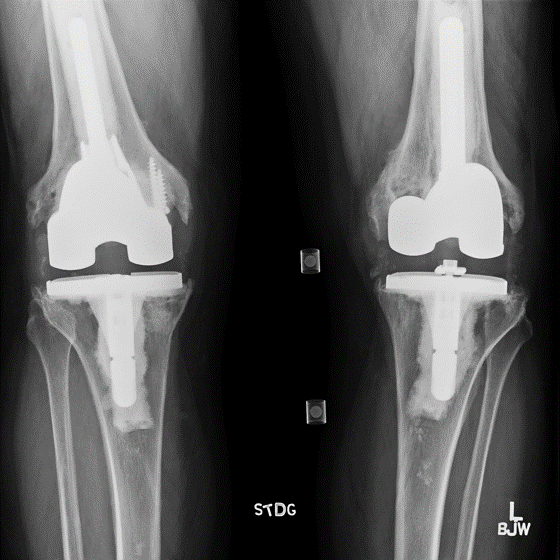

Case: 69 yo M w/ hx of left TKA w/ revision x 2 for aseptic loosening. Now with acute worsening left knee pain. Progressive radiolucent lines about femoral stem, change in modular junction appearance. Operative plan? How to address sclerotic canal of multiply revised knee?

Metallic stained soft tissue on approach. Modular junction failure. Stem and cement mantle removed en bloc. Pt underwent impaction bone grafting of polished/sclerotic canal. Cemented femoral stem with cone. https://t.co/hyA3fGNxF5